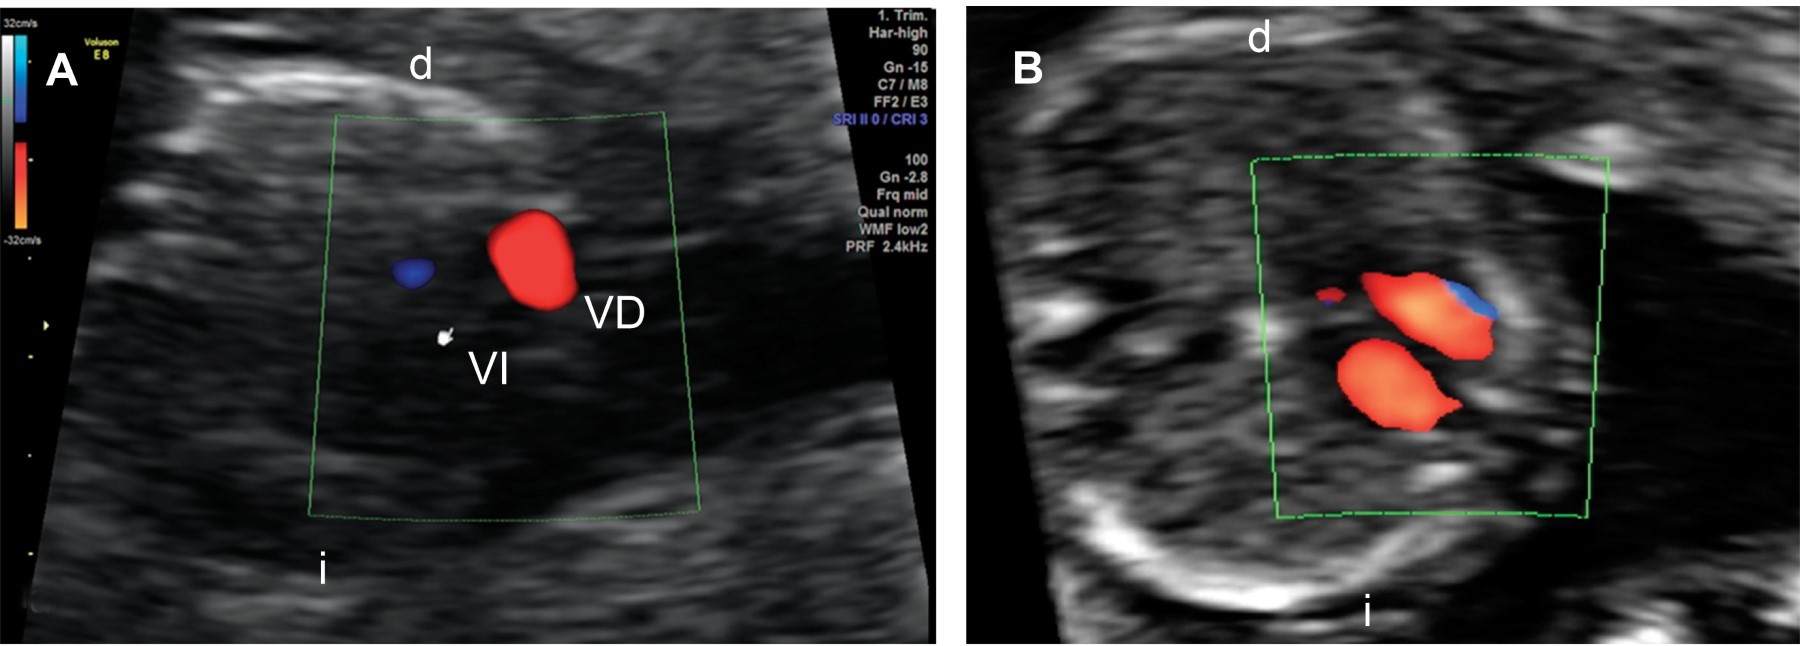

En la revisión cardiaca el corte axial de cuatro cámaras se observó anormal por ausencia de llenado del ventrículo izquierdo con Doppler color (Figura 1) y atresia mitral. En el tracto de salida izquierdo se identificó atresia aórtica y ausencia de flujo anterógrado. En el corte de tres vasos y tráquea se identificó la imagen en "V" con flujo reverso a través del istmo aórtico (Figura 2). Con estas características se integró el diagnóstico de SVIH.

Figura 2